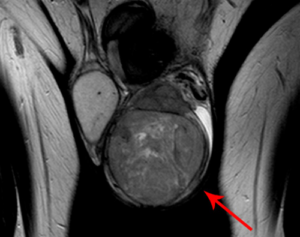

Фото показывает, как выглядит рак яичек у мужчин в разрезе

В свою очередь, герминогенные опухоли подразделяются на: